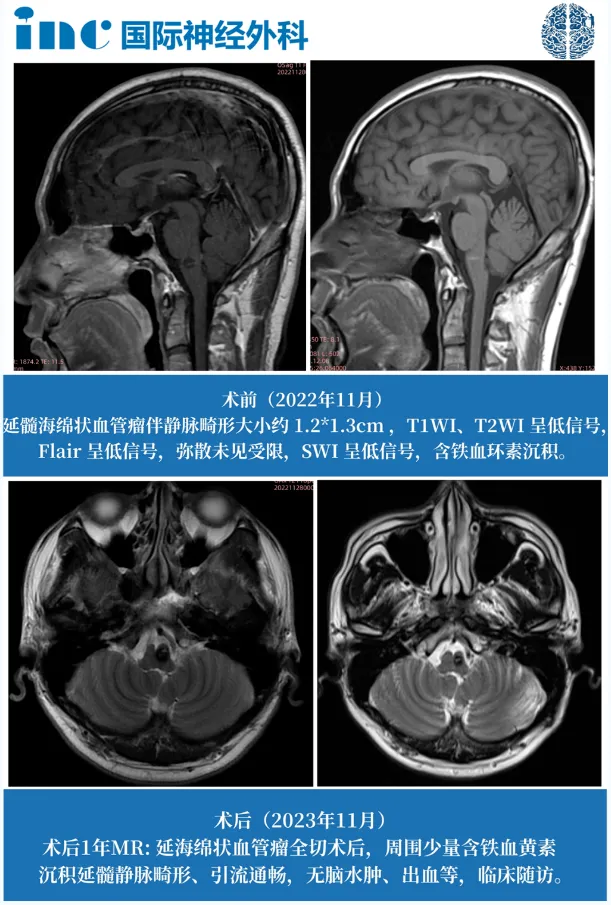

术前术后影像对比

巴教授术后影像对比

巴教授术后1年随访影像对比